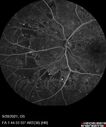

Macular ischemia left eye in type I diabetic (enlarged foveal avascular zone)213 views29 year old female with type I diabetes since age 5. Left eye has enlarged FAZ with vision of 20/20 OD and 20/60 OS. Both eyes have CSME. The left eye did have focal laserApr 12, 2023